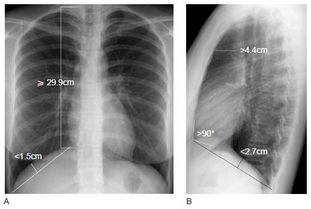

久而久之,肺泡就被這些氣體撐得越來(lái)越大,像是腫了一樣,醫(yī)學(xué)上就稱它為肺氣腫。專業(yè)來(lái)講,肺氣腫是由于慢性支氣管炎或其他原因逐漸引起的細(xì)支氣管狹窄,終末細(xì)支氣管遠(yuǎn)端氣腔過(guò)度充氣,氣腔壁膨脹、破裂而形成的肺臟過(guò)度充氣和肺容積增大的阻塞性疾病。